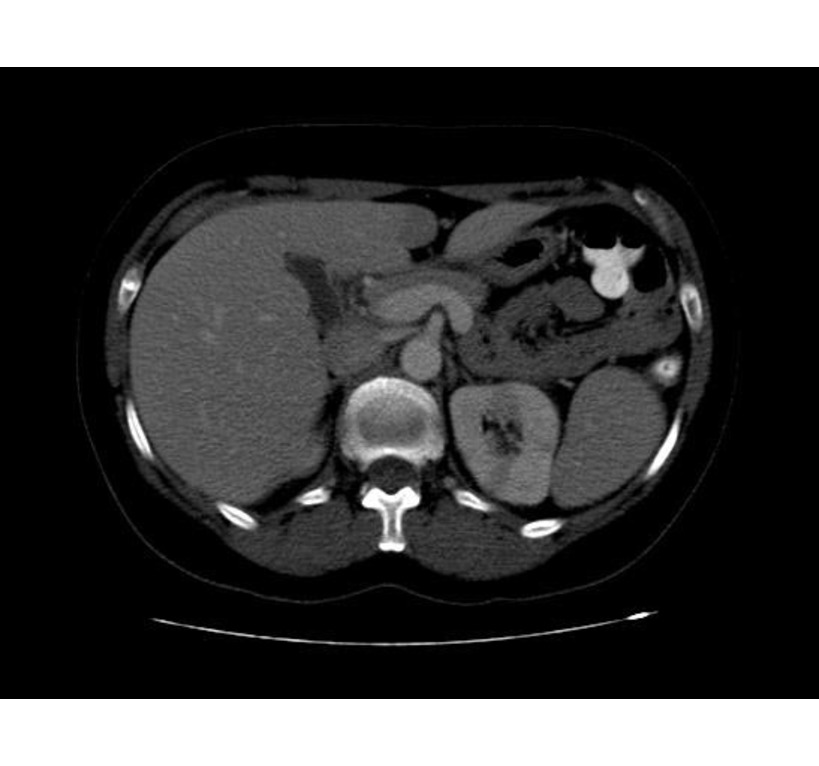

Ct search